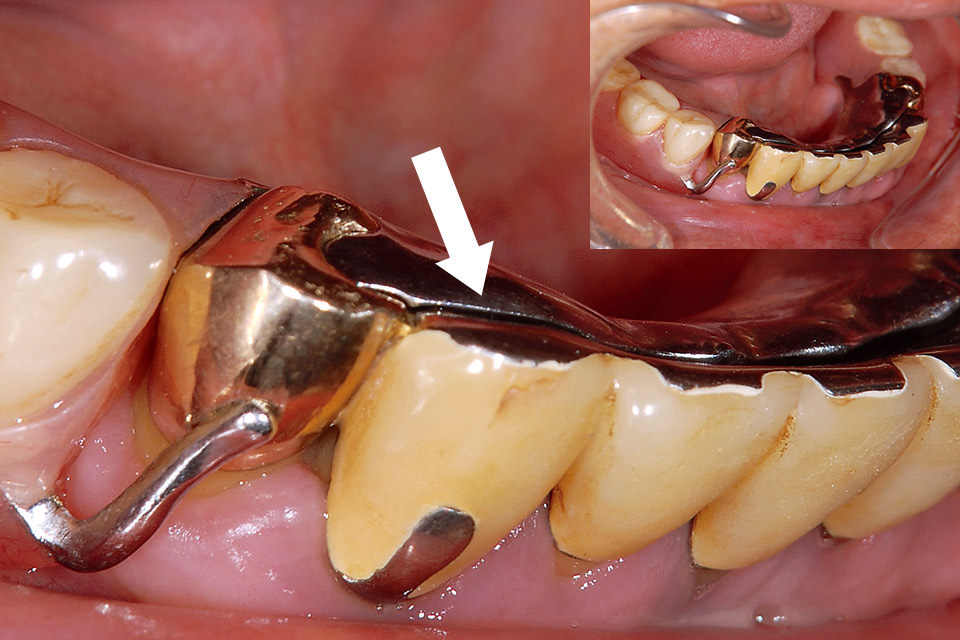

部分床義歯のリベース時にも、硬化途中に適度な硬さになった時点で一度口腔外に取り出して、アンダーカット部分を削除し、変形を防止するために再度口腔内に装着して硬化を終了させることが可能であり、難症例においてもストレスなく確実な操作が可能です。部分床義歯においては、無歯有床部にて沈下すると、鉤歯に対してクラスプは栓抜きのように作用するため、このような作用が継続的に発生するとクラスプとレストは鉤歯との適合を失い、鉤歯に不適切な力が持続的にかかることになりかねません。このような場合には、クラスプとレストを鉤歯に適合させた状態にてリベースし、その後咬合調整します。

図1-a 両側臼歯にて咬合すると無歯有床部が沈下して前歯部が不適合となる。

図1-b 前歯部を手指にて適合させた状態。